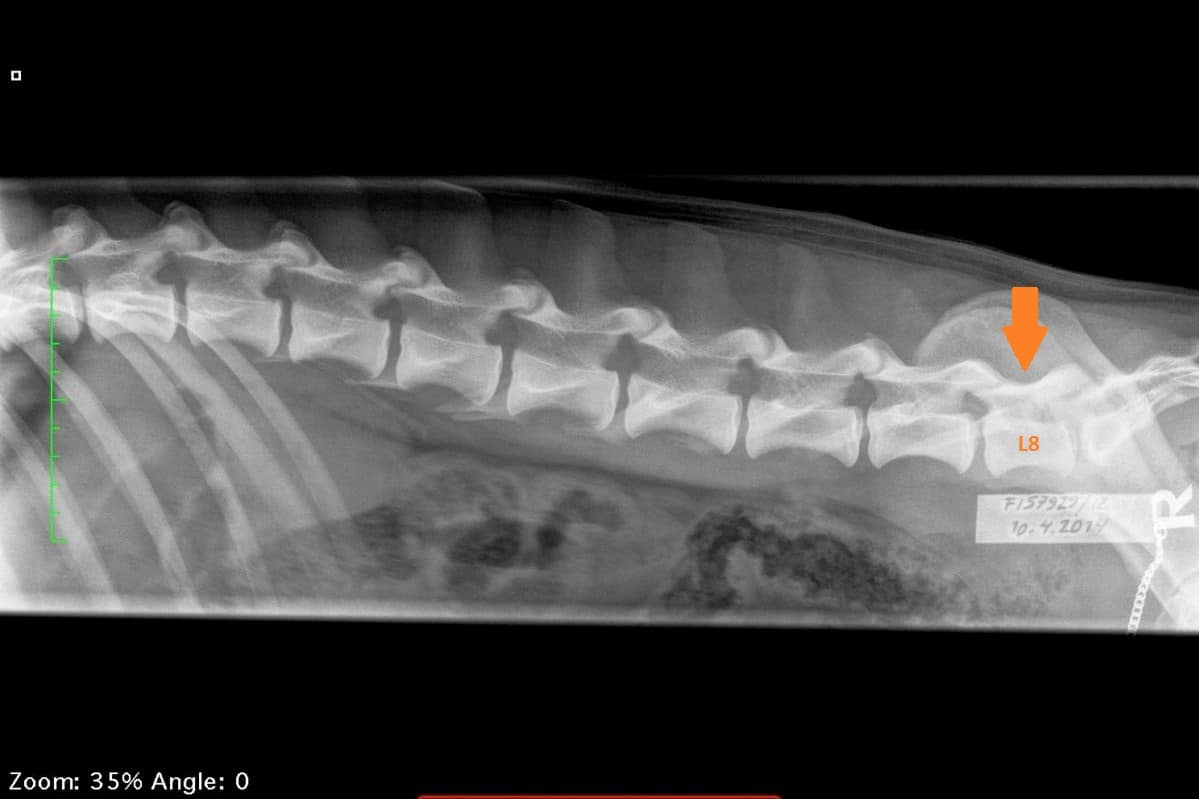

LTV4; 8 lannenikamaa. L8 on puhdas lannenikama ja siinä on normaalit okahaarakkeet.

Jotta voidaan tietää onko koiralla LTV tai ei on se röntgenkuvattava. Koiran selän pituus, lantion kulma, kinnerkulma tai mikään muukaan koiran ulkoisessa olemuksessa ei anna viitteitä siitä miten lanne-ristinikama on muodostunut. Koiralla, jolla on kahdeksan lannenikamaa, on täsmälleen sama nikamien kokonaismäärä kuin koiralla, jolla lannenikamia on seitsemän. Tällaisessa tapauksessa kahdeksas lannenikama on vain ominut itselleen toisen nikaman muodon!

Koiran normaali selkäranka koostuu seitsemästä kaulanikamasta (C1-7), kolmestatoista rintanikamasta (T1-13), seitsemästä lannenikamasta (L1-7) ja kolmesta ristinikamasta (S1-3). Nikamien laskenta aloitetaan ensimmäisestä rintanikamasta (T1). Häntänikamien CD) määrä vaihtelee.